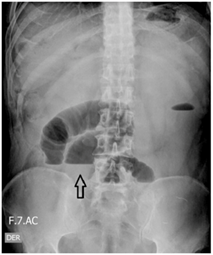

Con impresión diagnóstica de obstrucción intestinal se inició manejo con líquidos endovenosos, protección gástrica, analgésicos, antiespasmódico y antiemético. Se realizó paso de sonda nasogástrica y se obtuvo abundante material fecaloide. La serie radiológica de abdomen evidenció niveles hidro-aéreos y ausencia de gas distal (Figura 1).

Figura 1. Radiografía simple de abdomen donde se observan niveles hidroaéreos (flecha), indicando obstrucción intestinal